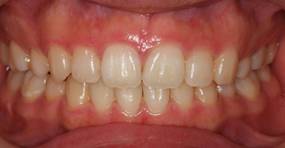

上顎前突+叢生 抜歯矯正(治療期間1年)

治療前、特に上の歯並びに問題がありました

奥歯のかみ合わせもよくありません

口元が突出しています

治療後、正中線も揃いました

小臼歯を抜歯しました

きちんと噛んでいます

大変きれいな横顔になりました。もともと明眸でしたので、矯正治療で明眸皓歯になりました。